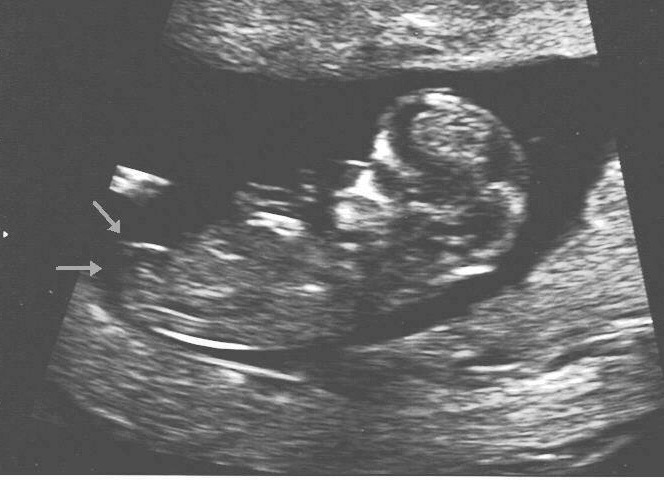

Thank you so much for helping me to understand the nub theory better. I'm sure it will take a while till I can figure them all out like you can. Below are all confirmed boy nubs- which is why I was uncertain about the white line in that recent nub post. I have read that it can be the hip bone and not necessarily the nub. Is that not true? Thanks again for your help. I appreciate your expertness :)

I didn't draw those arrows, by the way:Attachment 6599